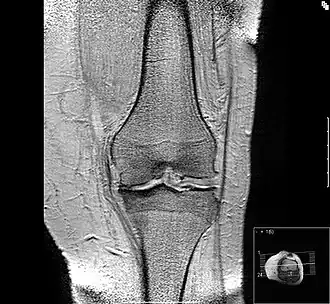

Der Patient berichtet bei der Anamnese über Gelenkschmerzen, anschließend muss geklärt werden, bei welchen Gelegenheiten dieser Schmerz auftritt. Es folgt die klinische Untersuchung der Gelenkkontur, der Funktion, der Bandstabilität, der umgebenden Muskulatur. Dann schließt sich, je nach Erfordernis, eine bildgebende Diagnostik an, wie beispielsweise Röntgen, Computertomographie (CT) oder Magnetresonanztomographie (MRT). Zeichen einer bestehenden Arthrose sind dabei eine Verschmälerung des Gelenkspaltes, Sklerose (eine reaktive Knochenverdichtung zu beiden Seiten des Gelenkspaltes), Osteophytenbildung an den Gelenkrändern und subchondrale Zystenbildungen des gelenkbildenden Knochens, die durch feine Rissbildungen des Knorpels und Durchtritt von Gelenkflüssigkeit in die darunter liegende Knochenschicht entstehen. Eine Verschmälerung des Gelenkspalts deutet dabei auf eine Arthritis oder eine Arthrose hin, je nachdem, ob der gelenknahe Knochen verdünnt oder verdickt ist.[17]

Durch eine Weiterentwicklung von Methoden zur Auswertung von MRT-Aufnahmen kann Arthrose bereits im Frühstadium erkannt werden.[18] Diese Technik ist auch für die Erforschung neuer Medikamente als therapiebegleitende Verlaufskontrolle von großer Bedeutung.